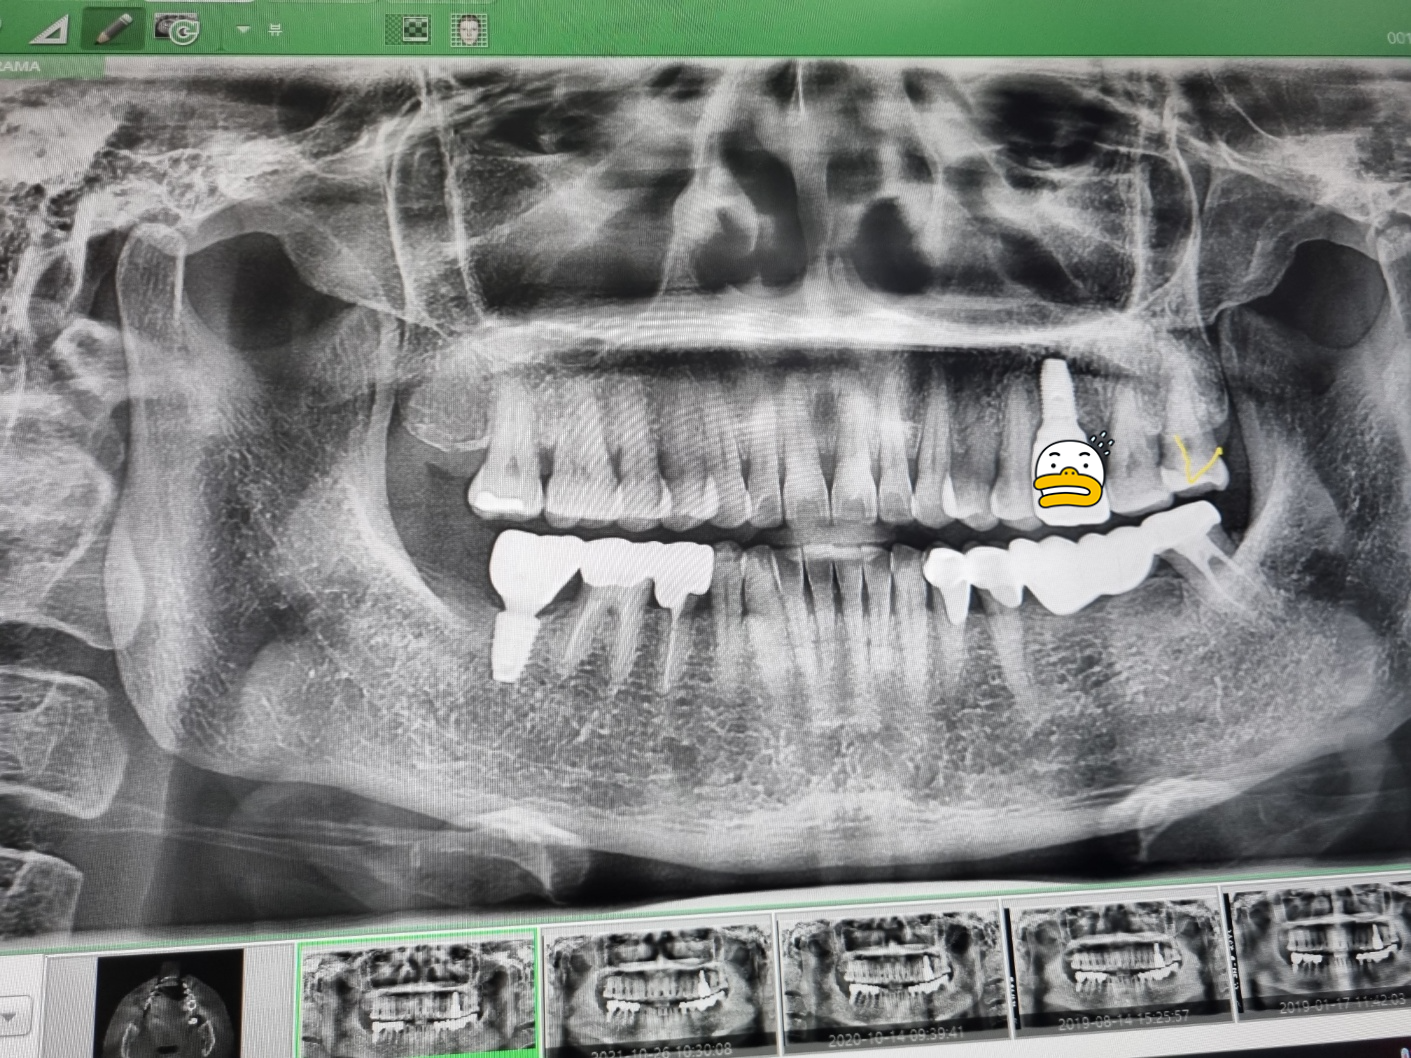

맨 끝에 노란색으로 표시한 부분이

이번에 치료를 받은 사랑니예요

그리고 벌써 임플란트를 한 지 5년이 지난

윗치아의 뿌리와 머리 부분을 연결해 주는

나사 부분도 메꾸어 주셨는데요